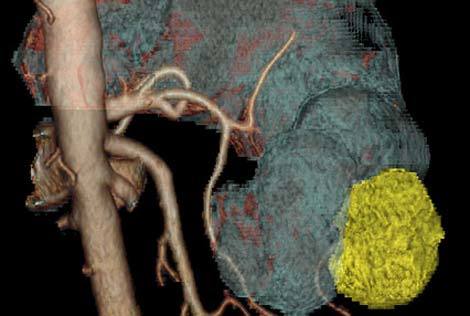

Loại bỏ các cơ quan nội tạng thiết yếu

Đầu năm 2009, bé gái Heather McNamara, 7 tuổi, đã sống sót qua một cuộc phẫu thuật kéo dài 23 giờ, loại bỏ 6 cơ quan quan trọng của em nhằm triệt hạ một khối u đe dọa tính mạng. Các bác sĩ phẫu thuật ở New York, Mỹ đã buộc phải cắt bỏ tuyến tụy, gan, dạ dày, lá lách cũng như ruột non và ruột già của Heather để triệt tận gốc một khối u ung thư có kích thước của một quả bóng chày. Nhóm chuyên gia cũng đã tạo cho cô bé một dạ dày nhân tạo từ mô ruột để chứa đồ ăn thức uống.